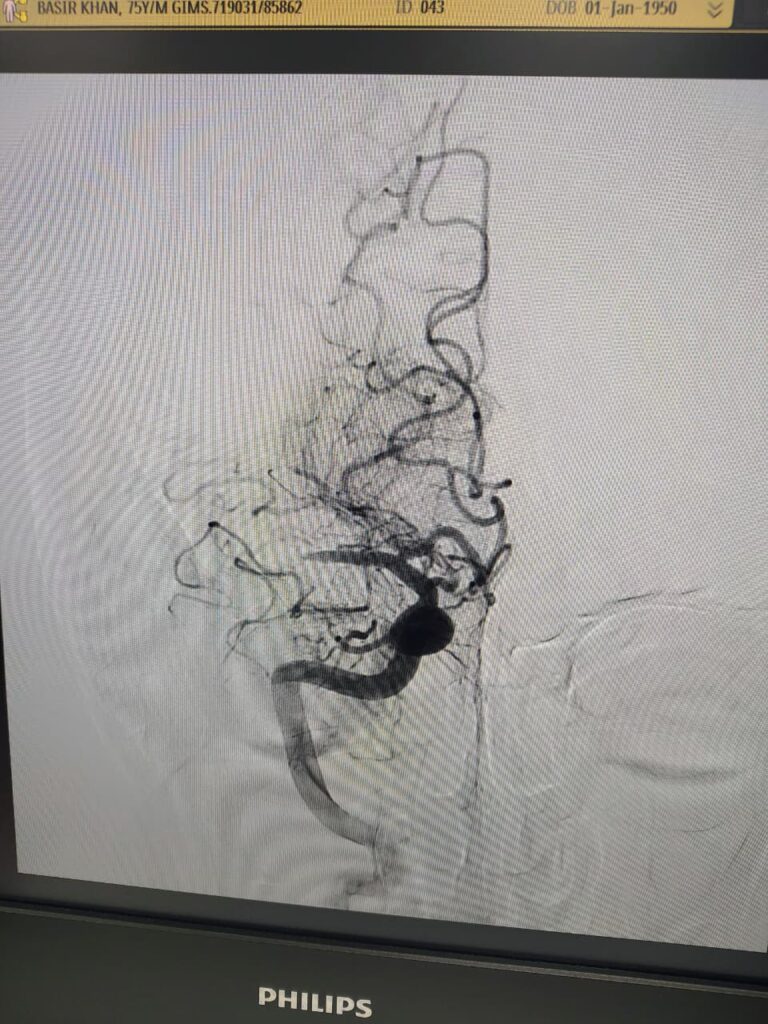

Case 4

Ruptured Brain aneurysm (left ICA communicating segment wideneck aneurysm) treated with Stent Assisted Coiling.

Coiling in live case

after complete coiling and stenting

final result complete coiling and Stenting of brain aneurysm